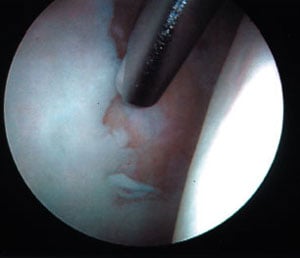

Torn labrum at rim of socket

Through the second opening (portal) instruments are inserted to shave tissue, cauterize structures, or remove pieces. On occasion, holes may be drilled into patches of bare bone where the cartilage has been lost. This technique, called "microfracture" or "picking" incites localized bleeding and encourages the formation of fibrocartilage (repair cartilage). Saline is pumped through the joint during the procedure to improve visualization and flush out debrided tissue.